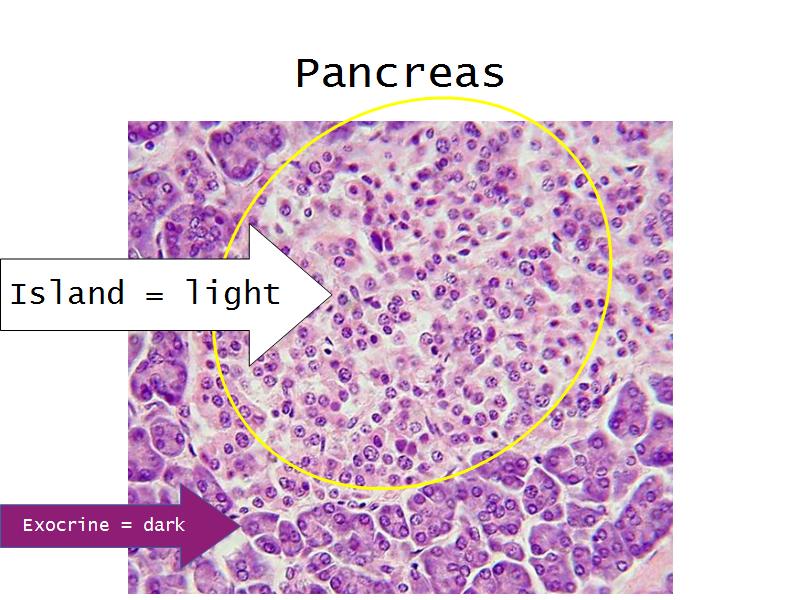

- Pancreas

- C3: Pancreas

- C3: Pancreas = glucagon, insulin, somatostatin, pancreatic polypeptide

- C4:Thyroid gland = thyroxine, triiodothyronine

- F4: Alpha cells = pancreas

- Slide 50: Pancreas